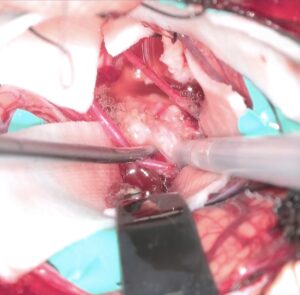

左海綿静脈洞内髄膜腫(複視)に対して、現在のスタンダードは放射線治療になりつつありますが、これも長期制御が困難なので、今回はBTOで左内頸動脈閉塞による血管内腫瘍塞栓を行う計画としました。それに先立ち、BTO時のStump <50mHgであったためSTA-MCAバイパスを行いました。